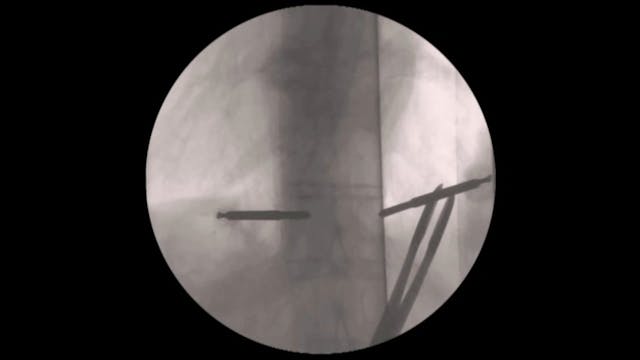

This video demonstrates how to perform a replacement of vertebral body in the thoracolumbar spine via a mini-open transthoracic approach in a posttraumatic kyphosis.